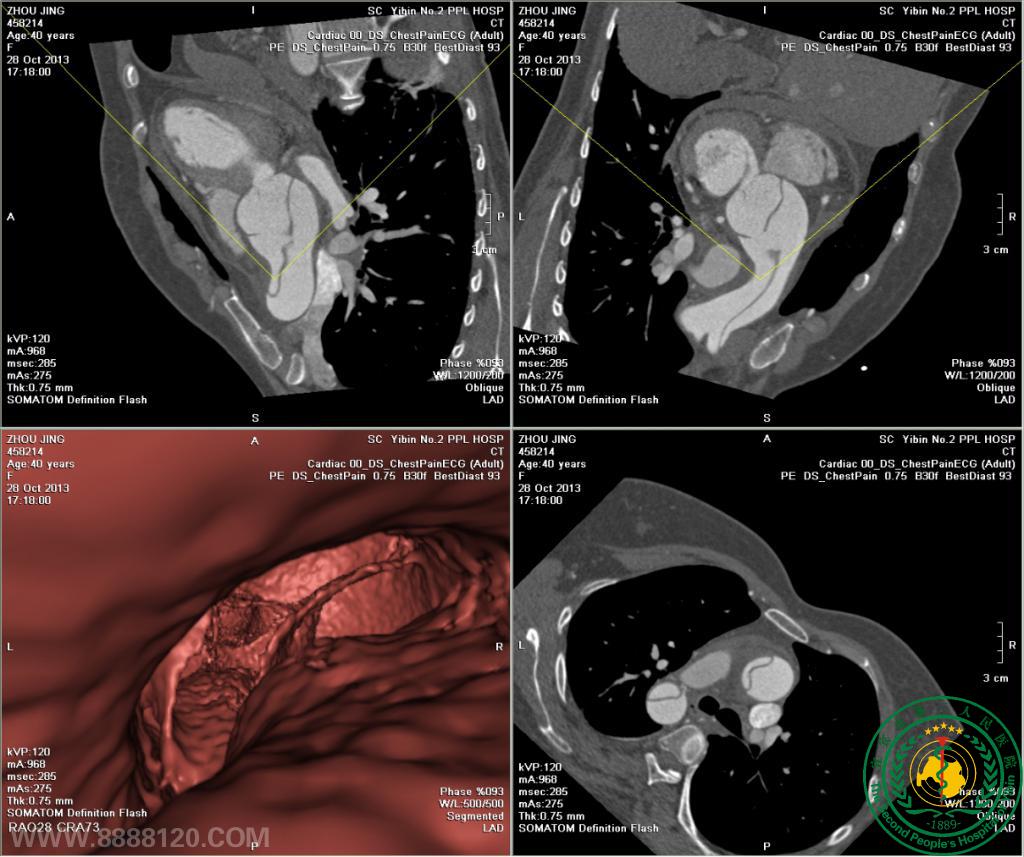

例二 一次扫描冠状动脉术后评价 双侧肺动静脉和主动脉未见异常(图1),右侧桥血管栓塞,余左侧二支桥血管未见异常(图2)

我院CT室推出胸部血管(冠状动脉、肺动静脉、主动脉)一站式检查技术我院CT室推出胸部血管(冠状动脉、肺动静脉、主动脉)一站式检查技术